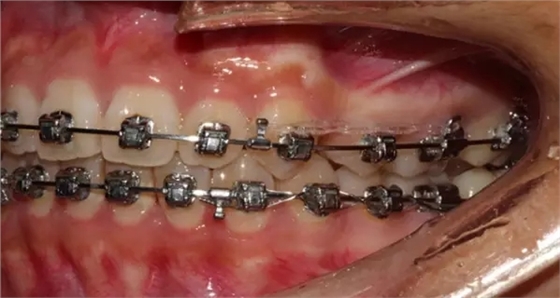

上下牙列擁擠,磨牙尖牙Ⅱ 類關(guān)系,3 度的深覆牙合,上頜中切牙伸長內(nèi)傾拔除上頜雙側(cè)的第一前磨牙,先粘上頜高轉(zhuǎn)矩的自鎖托槽排齊牙列,唇向開展上頜切牙,有一定的覆蓋,粘下頜標準轉(zhuǎn)矩托槽,上頜 1, 2 之間植入種植支抗壓入,同時后牙 5, 6 之間植入種植支抗內(nèi)收前牙,打開咬合關(guān)閉間隙。治療關(guān)鍵:前牙轉(zhuǎn)矩的控制第 1 個月 上頜粘上 Damon Q 高轉(zhuǎn)矩托槽,上 .014 熱激活 NiTi 絲。第 3 個月 上換 .014 x .025 熱激活 NiTi 絲。第 5 個月 上頜基本排齊,覆蓋增大,上換 .017 x .025 NiTi絲,下頜粘托槽,下 .014 熱激活 NiTi 絲。第 7 個月 上 .017 x .025 NiTi 絲加搖椅,下?lián)Q .014 x .025 熱激活 NiTi 絲第 9 個月 上頜換 .019 x .025 NiTi 絲加搖椅,下頜換 .017 x .025 NiTi 絲第 11 個月 下頜換 .019 x .025 加搖椅,上頜 1, 2 之間, 5, 6 之間植入種植釘,下頜出現(xiàn)散隙。第 13 個月 上頜換 .019 x .025ss 加搖椅,前牙種植釘用 Power Chain 壓低前牙(每側(cè) 100g),后牙種植釘關(guān)閉間隙(每側(cè) 150g),下?lián)Q .019 x .025ss,Power Chain 關(guān)閉間隙。第 19 個月 上頜前牙基本壓低到位去除前牙種植釘,繼續(xù)用關(guān)閉間隙,下頜散隙關(guān)閉。

第 22 個月 上頜覆蓋變小,去除 5, 6 之間種植釘,后牙前移關(guān)閉間隙。第 30 個月 患者未配合中線牽引,下中線仍有 1mm 右偏,患者對矯治效果滿意要求拆除,拆除固定矯治器,取模制作壓模保持器。 1.骨性 Ⅱ 類的患者內(nèi)收前牙時需對上頜前牙的轉(zhuǎn)矩進行較好的控制才能獲得良好的面型和唇部形態(tài)。 2.露齦笑的患者治療前要分析其病因是唇、牙齦、牙齒、牙槽骨、上頜骨或多種因素結(jié)合,再制定矯治方案。 3.Ⅱ 類第二分類伴露齦笑的患者的上頜前牙移動軌跡是唇向開展-壓低-整體內(nèi)收。 4.Ⅱ 類第二分類牙齒舌傾比較厲害的情況,上頜中切牙慎用樹脂咬合墊。 5.壓低前牙或控根移動時容易發(fā)生牙根的吸收,需輕力緩慢的移動。